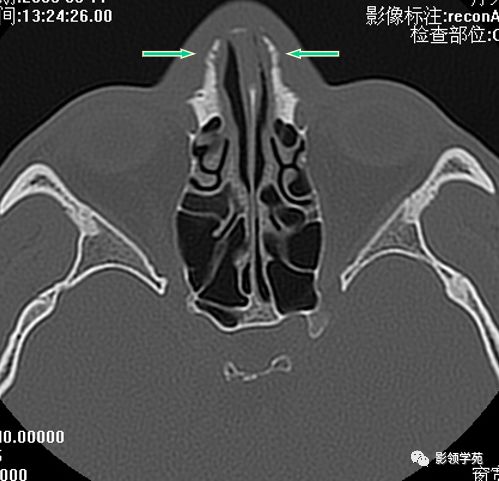

双侧鼻骨骨折

双侧上颌骨额突骨折

鼻中隔骨折